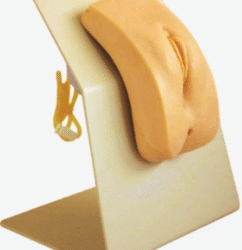

ATL-127 PALM ANATOMY